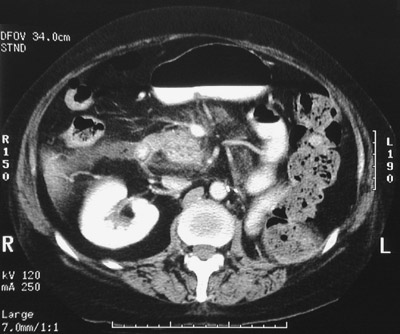

This axial CT scan of the abdomen reveals the

right kidney

, but the left kidney is absent following nephrectomy for renal cell carcinoma.